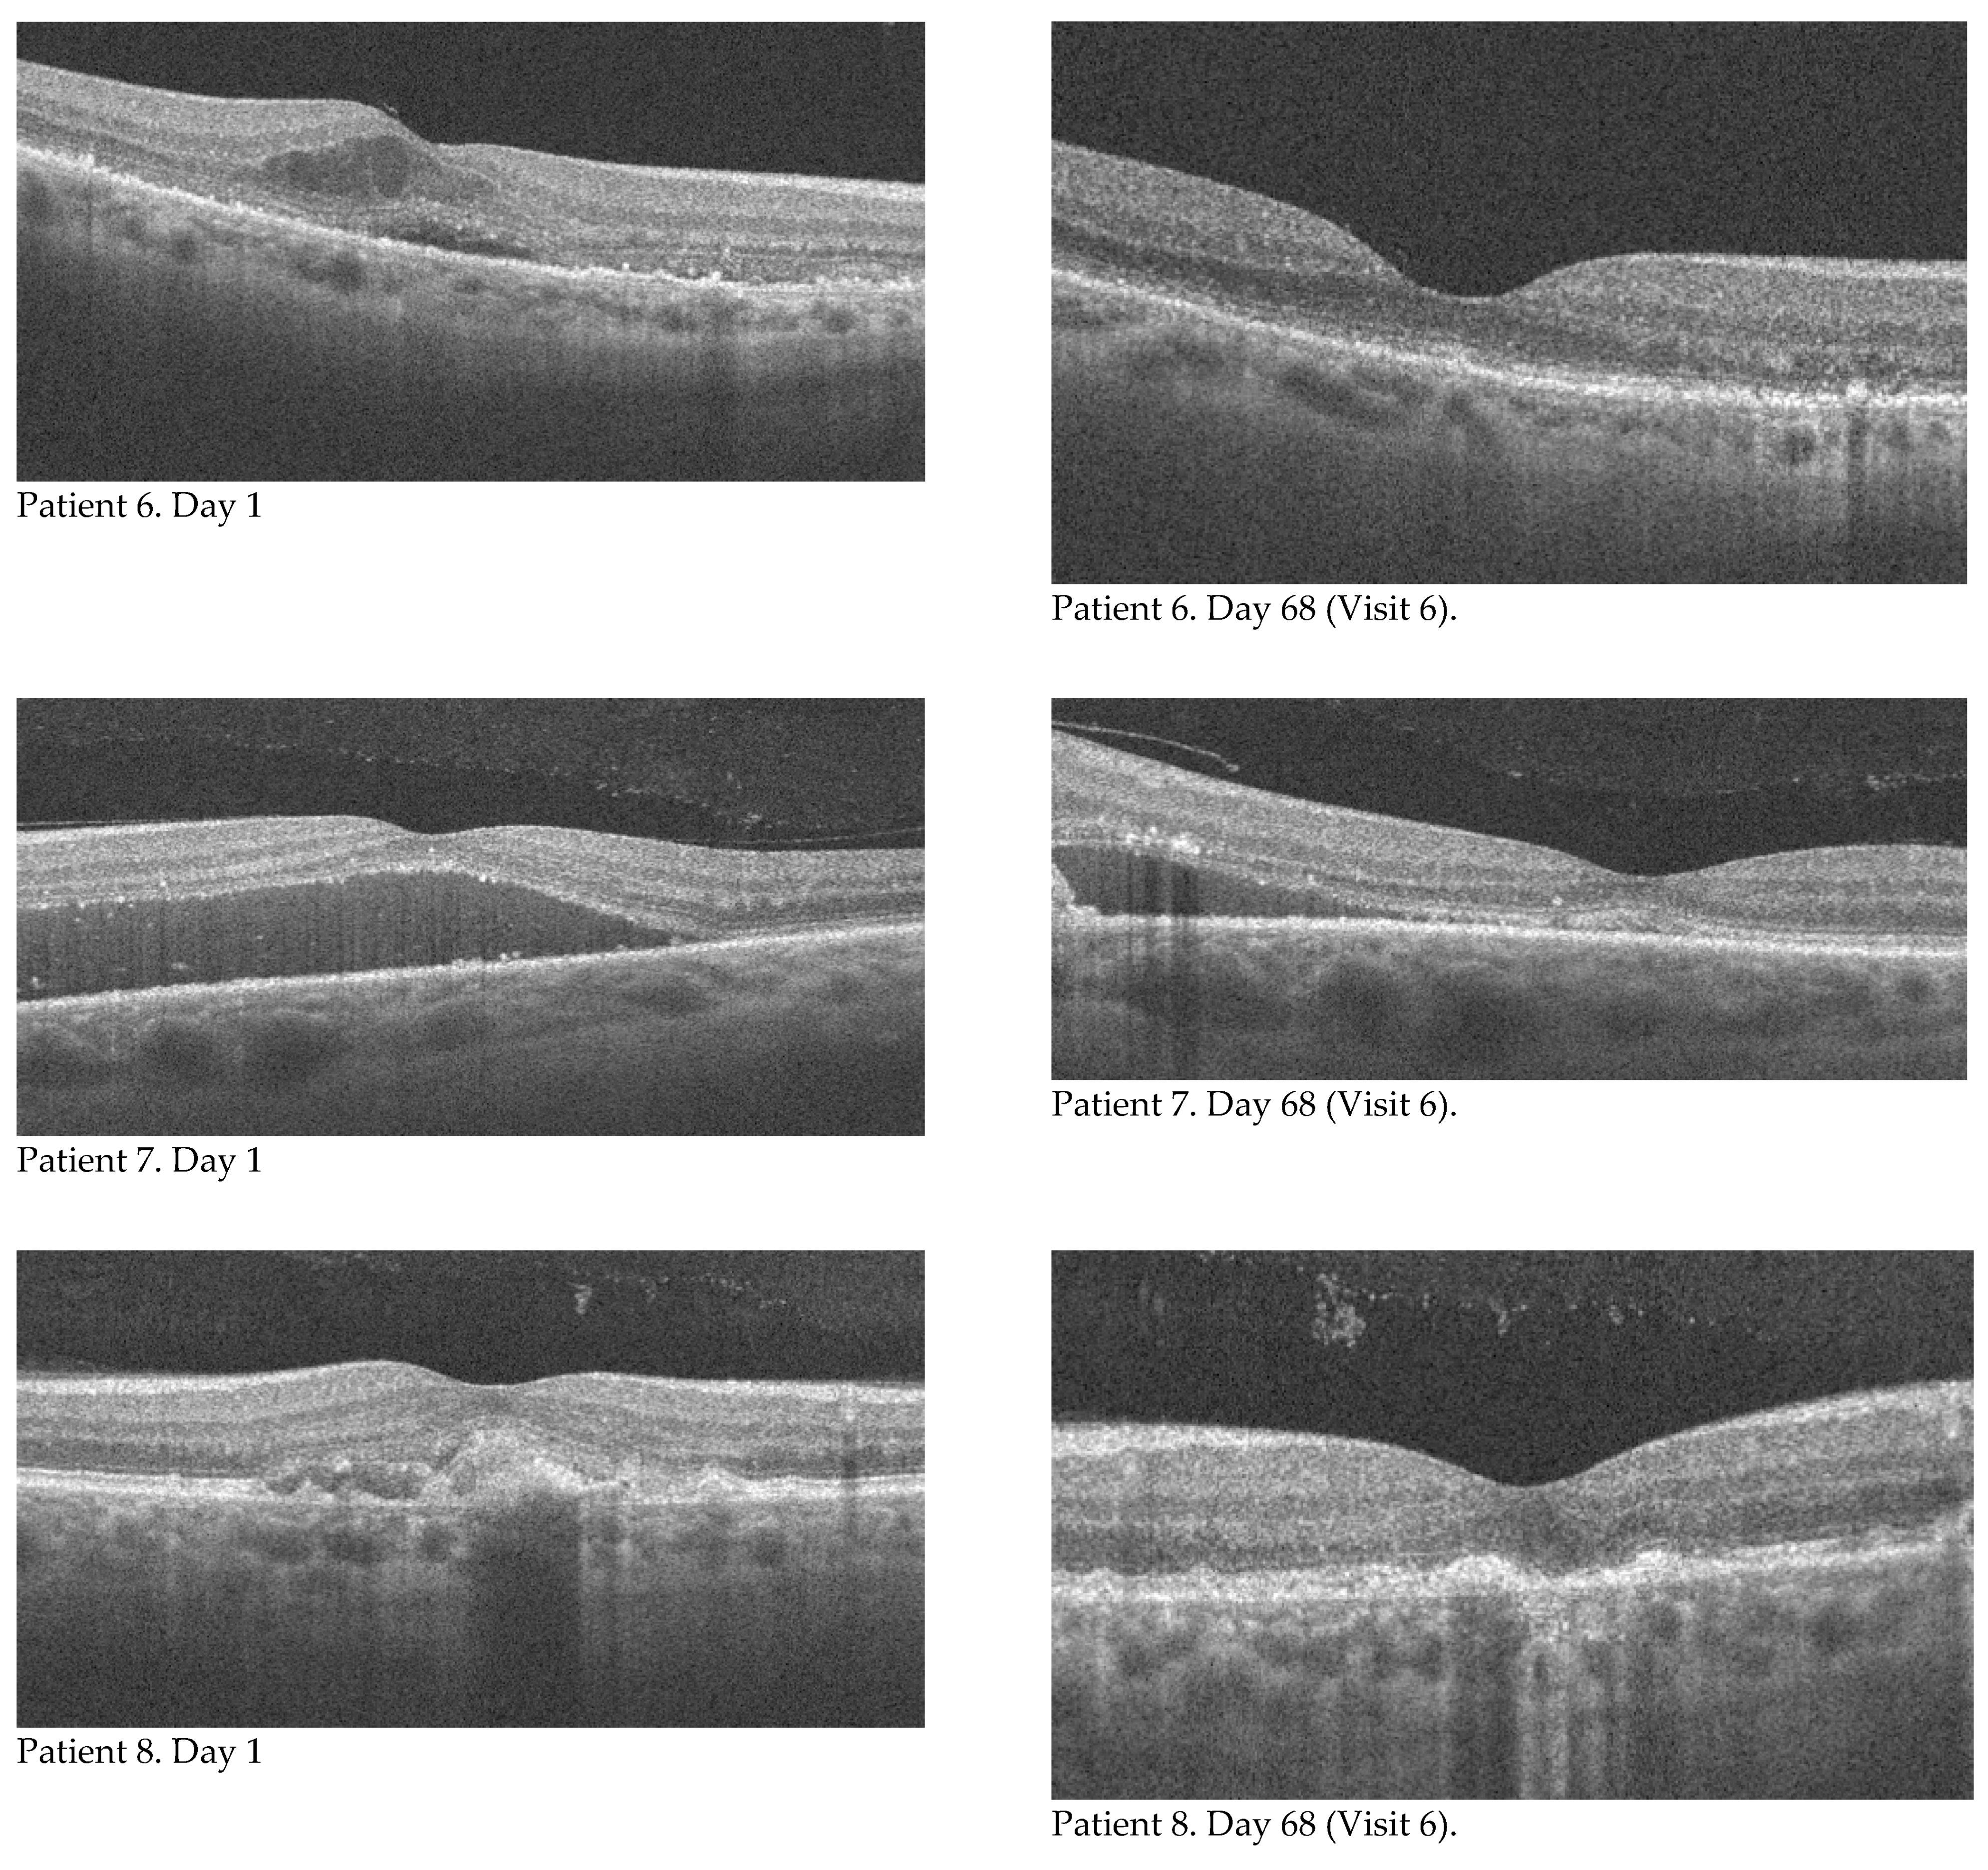

Figure 1. Changes in BCVA in subsequent measurements. Colour indicates statistically significant differences between two consecutive measurements. The change in central retinal morphology as seen on OCT (B-scan) in individual patients on day 1 of injection and day 97 (endpoint) is shown above.

The mean value of best corrected visual acuity (BCVA) increased with each visit. The results recorded in the study group along with the standard deviation value are shown in Table 2. The Student’s t test for dependent samples showed a significant difference already between the baseline value (BCVA_1) and the measurement taken seven days after the first injection at the follow-up visit (BCVA_2). This relationship and the changes in BCVA in subsequent measurements are shown in Figure 1. The value of best corrected visual acuity continued to increase at subsequent measurement points, but the differences between successive results were not statistically significant. The total change in BCVA during the course of the therapy was also analyzed by comparing the baseline value (BCVA_1) and the result of the last follow-up visit, that is, seven days after the third injection (BCVA_6). The mean change in the studied group was 14.5 letters (SD = 9.61). There was no improvement in one patient (the final value corresponded to the baseline value). This was most likely related to the presence of focal sub foveal photoreceptor atrophy, already present at the time of treatment initiation. An improvement in BCVA ranging from 9 to 30 letters.